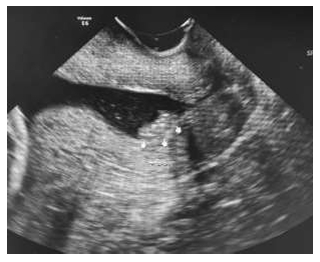

Paciente 21 anos, primigesta, na 20ª semana de gravidez e assintomática. Veio a emergência trazendo uma ultrassonografia com o exame abaixo.

A mesma foi encaminhada pelo ultrassonografista, pois deveria procurar uma emergência.

Baseado nas recomendações atuais, assinale a alternativa CORRETA.